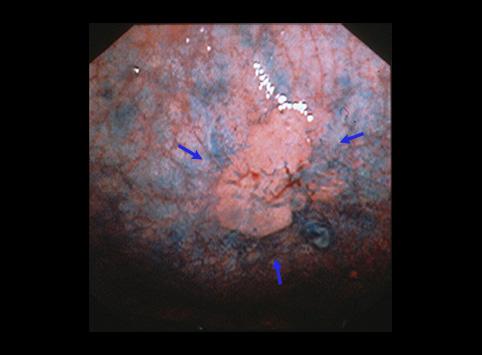

疾病(病理主体)的分类恶性上皮性肿瘤/腺癌

部位(按器官分)胃(部位)/体部

检查方法内窥镜

肿瘤的肉眼分类0型(表在型)/IIc型(IIc)

肿瘤最大直径15~19

肿瘤的深度sm